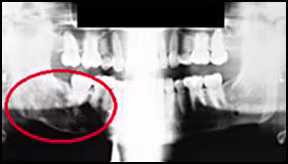

Images demonstrating how inadequate exposure can lead to failure to detect pathologic features. The image on the right is a digitally enhanced version and clearly demonstrates the appearance of an impacted mandibular right third molar that was not readily apparent on the original (left). This enhancement also clearly demonstrates a large pericoronal lesion that involves the right mandibular third molar.